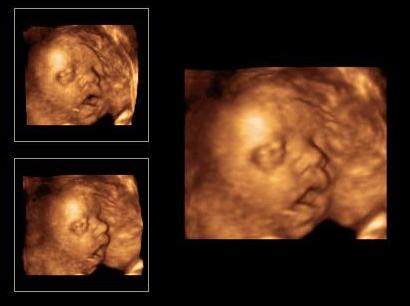

A Milán amúgy végig magyarázott :shock: :D folyamatosan járt a szája ...láttuk ahogy hatalmasra nyitja a száját még az orrát is felhúzta és majszolja a köldök zsinórt,ami pont az arca előtt van nagy kupacba...ezért nem látszott teljesen a pofija.

Teszek róla képet de nem sok látszik belőle max az orra h felhúzta ...meg ha jól megnézitek látszik,hogy mekkora a szája és benne van a zsinór :D Kép